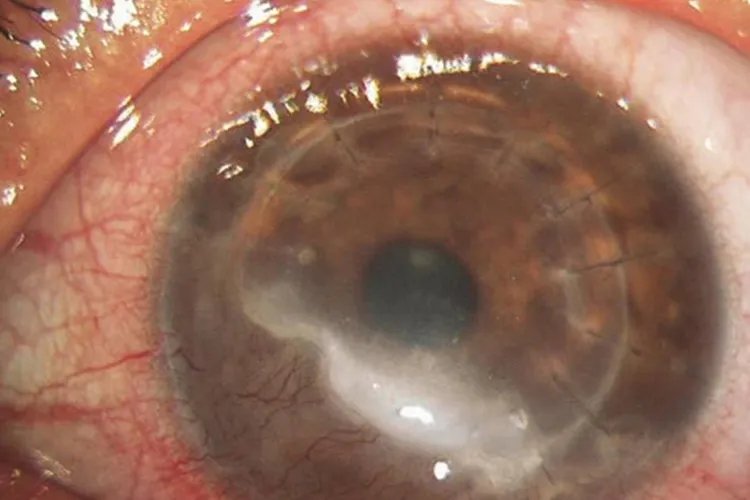

的有关信息介绍如下:概述角膜炎初期症状多见于角膜上皮病变,常为角膜溃疡、水疱、浑浊等。临床上可将角膜炎分为感染性角膜炎和非感染性角膜炎。角膜炎病因较多,与外界或内源性致病因素侵袭角膜组织相关。症状感染性结膜炎细菌性角膜炎本病起病急骤,病变早期表现为角膜上皮溃疡,溃疡下有边界模糊、致密的浸润灶,周围组织水肿。

真菌性角膜炎起病缓慢,亚急性经过,临床表现早期症状较轻,发展缓慢,为角膜浅层溃疡。单纯疱疹病毒性角膜炎单纯疱疹病毒性角膜炎中上皮型结膜炎初期病变显著。上皮型角膜炎感染初期角膜上皮层可见灰白色、近乎透明、稍隆起的针尖样水疱,点状或排列成行或聚集成簇,一般仅持续数小时至十余小时,因此常被忽略

棘阿米巴角膜炎感染初期表现为上皮混浊、微囊样水肿或假树枝状,上皮可完整,少数患者可出现特征性放射状角膜神经炎。